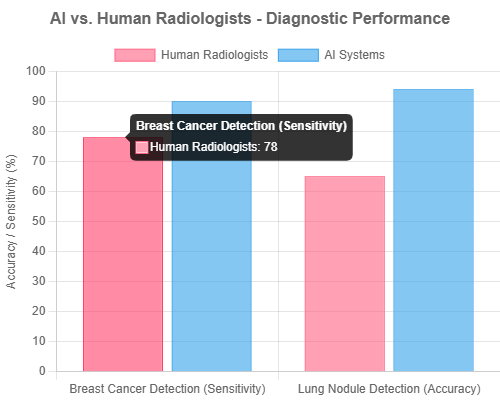

- Enhanced Diagnostic Accuracy: AI in Medical Equipment has demonstrated remarkable performance in various diagnostic tasks. For instance, an AI system achieved 94% accuracy in detecting lung nodules from medical images, significantly outperforming human radiologists who scored 65% in the same task (Scispot.com, May 31, 2025). Similarly, AI-based diagnosis has reached 90% sensitivity in breast cancer detection, compared to 78% for radiologists (Scispot.com, May 31, 2025). In emergency medicine, AI-based imaging systems have shown 85-90% accuracy in disease detection from X-rays and CT scans (PMC, Apr 1, 2025).